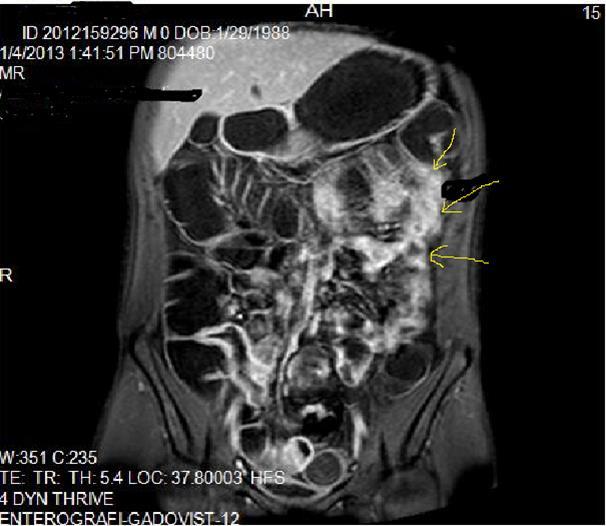

Pathognomonic signs of Crohn’s disease are; Bowel wall thickness must be higher than 2 mm in small intestine, 3 mm in colon, valvula conniventes has to be less than 3 mm, and small intestine diameter will be less than 3 cm, long segment intestinal infiltration, creeping fat sign, loss of haustration in colonic segments, skip lesions between normal and diseased segments and transmural invasion of bowel wall2, 5, 12, 14,18, 19, 20. In endoscopy; Aftos ulcerations and erosions are found out initially in the normal bowel mucosa than at later stages, mural stratification with longitudinal and transverse ulcerations are observed7, 14, 20, 21. On MRI; High bowel wall enhancement is particular at active inflammation, increased signal at bowel wall and adjacent mesentery on T2W images, strictures-fistulization and abcesses are the main complications and hyperintense on T2W images, asymmetrically thickened mucosal folds and lymphadenopathy, mesenteric stranding of the effected bowel wall and prominent draining vessels of the inflamed intestinal loops(comb sign), presence of intramural fat at chronic phase and target sign due to wall thickening at acute phase, surrounding peri-intestinal edema in acute phase are the main findings of Crohn’s disease7, 12, 14,18, 19, 20, 21 (Figure 2a-b)

Mucosal irregularities and ulcerations, strictures and fistulas at chronic stage can also be visualized by enteroclysis3, 4, 14, 15, 22 (Figure 3a-b-c).Clinical signs of Crohn’s disease are; Abdominal ache, diarrhea, fever, loss of weight, malnutrition, hemorrhage and fistulas, its extra-intestinal manifestations are: Arthritis, iridocyclitis, erthytema nodosum, aftoz stomatitis, cholelithiasis, primary sclerosing cholangitis and ankylosing spondylitis8, 9, 10, 11, 12, 13, 14, 15, 16,20, 21, 22.In the differential diagnosis; Ulcerative colitis(UC), ischemic colitis(IC), infectious-fungal and tuberculous(Tbc) enteritis, radiation enteritis, Lymphoma, Behcet’s disease have to be thought5, 6, 7,18, 19, 20, 21 . UC involves the entire colon, small intestine involvement is extremely rare, it tends to involve only the mucosal part of bowel with continuous pattern and skip lesions-transmural pattern of Crohn’s disease involvement can never be seen in UC, fistulization and abscess formations are not evident, terminal ileum involvement of UC is named as backwash ileitis, UC is a pre-malignant inflammatory disease which often causes rectal adenocarcinoma, Malignant transformation of Crohn’s disease is extremely rare 6, 8, 10, 14, 18, 19

Figure 2a.Concentric luminal narrowing, mural and transmural involvement of terminal ileum due to Crohn’s disease in T2W coronal sequence after OCA application.

Figure 2b.Curvi-lineer, diffuse peripheral enhancing bowel wall in the terminal ileum on axial T1W post-contrast image.

Figure 3a-3b-3c.Diffuse mucosal involvement and extreme luminal narrowing in the terminal ileum due to Crohn’s disease on T2W coronal sequence after OCA administration, stricture and string sign near ileo-ceccal valve in Figure 3b.